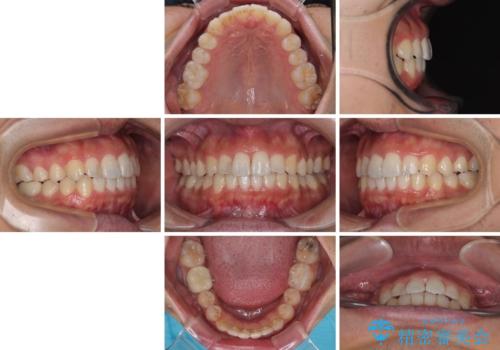

前歯のデコボコと突出感をマウスピース矯正できれいに

矯正治療後に銀歯をセラミックに替えたいとの要望があり、概ね歯列が整ったところで銀歯をセラミックに替え、仕上げにインビザライン1セットを使用して最終的に歯列を整えました。